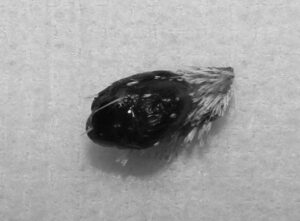

右目の瞼にできたデキモノを気にされて来院されました。切除手術を行い元気に退院しました。病理組織検査の結果は良性の「黒色細胞腫」でした。病理コメント:メラニン産生細胞に由来する腫瘍です。腫瘍細胞はやや高い細胞異型性を示しますが、高倍率10視野における核分裂数が3個を越えていないため良性と判断しました。切除マージンは確保されていますが、念のため今後の経過にはご注意ください。